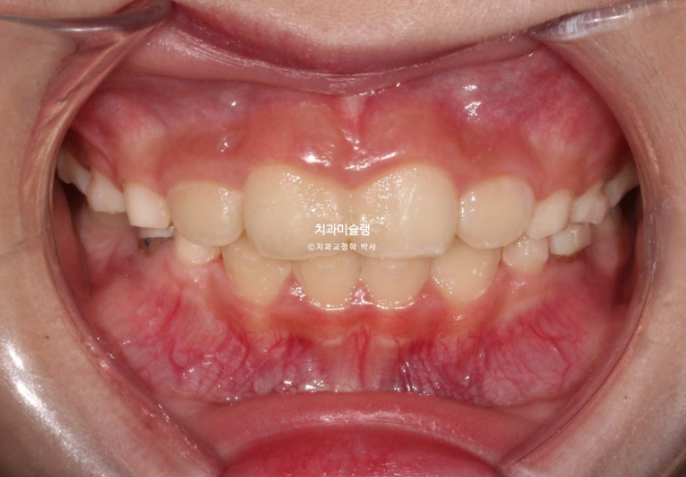

23년 10월, 교정치료를 위해 온 어린이 입니다.

앞니 두 개 높낮이 차이, 앞니가 깊게 물리는 과개교합이 보입니다.

앞니 네개 중 옆 앞니 즉 측절치가 나올 공간이 좁습니다.

어린이 교정은 악궁확장을 통해 이가 날 공간을 넓히는 과정이 동반이됩니다.

인비절라인 퍼스트 치료에 들어갔습니다.